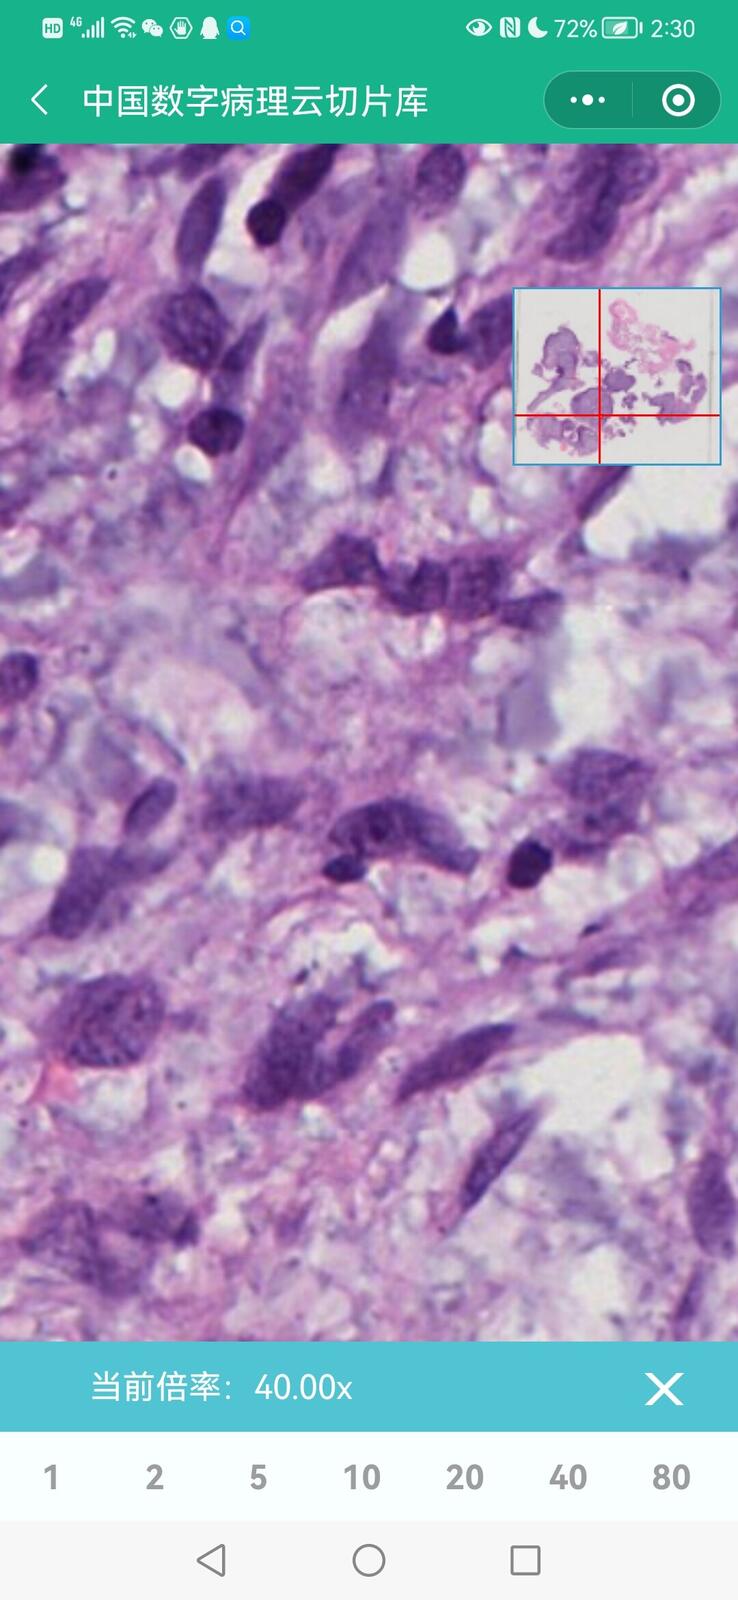

乳腺黏液性囊腺瘤伴导管内癌

乳腺多形性脂肪肉瘤

乳腺叶状囊肉瘤

乳腺分泌性癌(29岁)